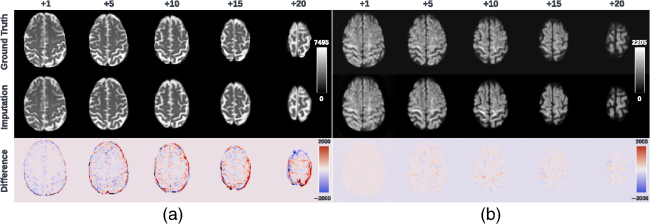

Fig. 6 Axial slice imputations for b0 images (a) and b1300 images (b). The color lookup tables are adjusted with different intensity ranges for a better display of diffusion-weighted volumes. Each column represents the distance to the nearest acquired slice in millimeters (mm). Red and blue indicate that the imputed intensity is larger or smaller than the ground truth reference, respectively. Consistent with Fig. 5, the proposed framework performs imputations that globally align with the ground truth reference, albeit with a blurrier appearance. In addition, increasing imputation errors are observed as the distance of the imputed slices increases, for both b0 and b1300 images.